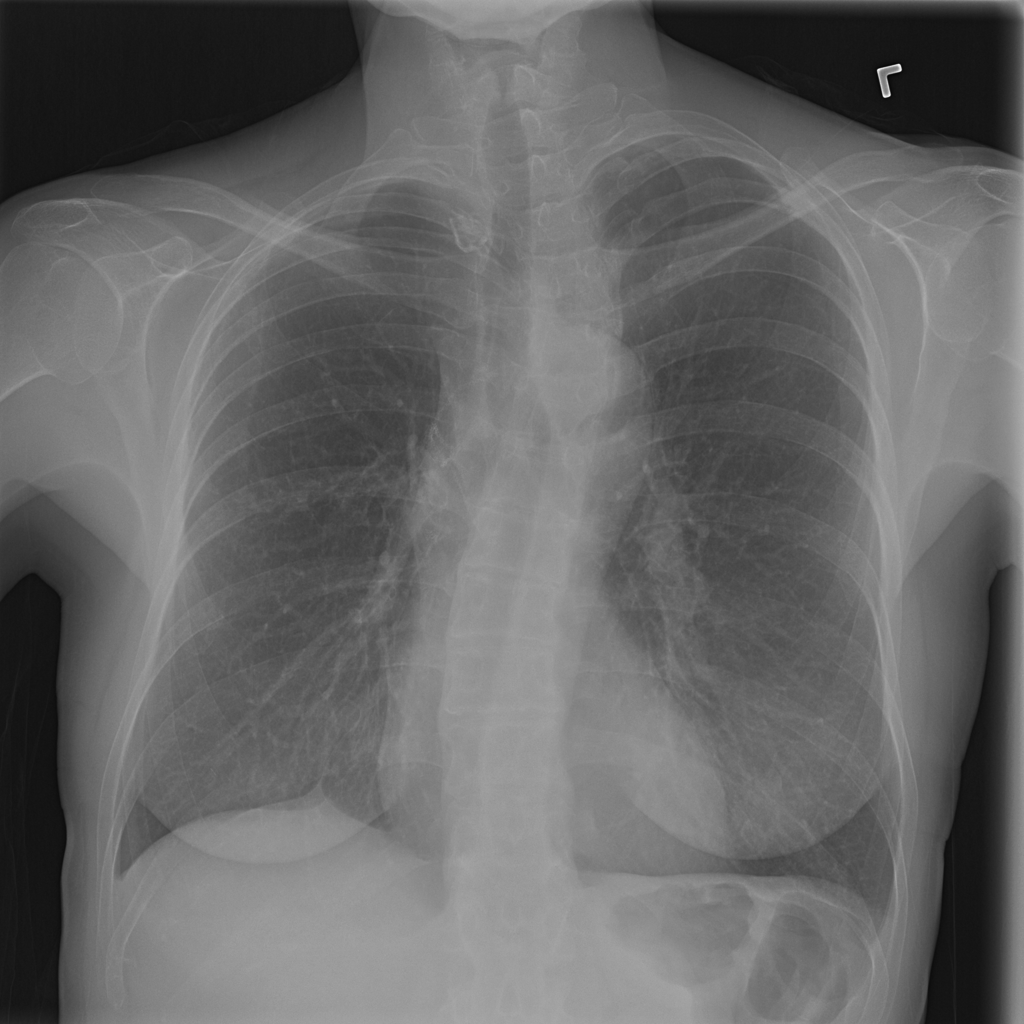

PAT-0E82 · IMG-000Emphysema

PAT-0E82 · IMG-000

AP